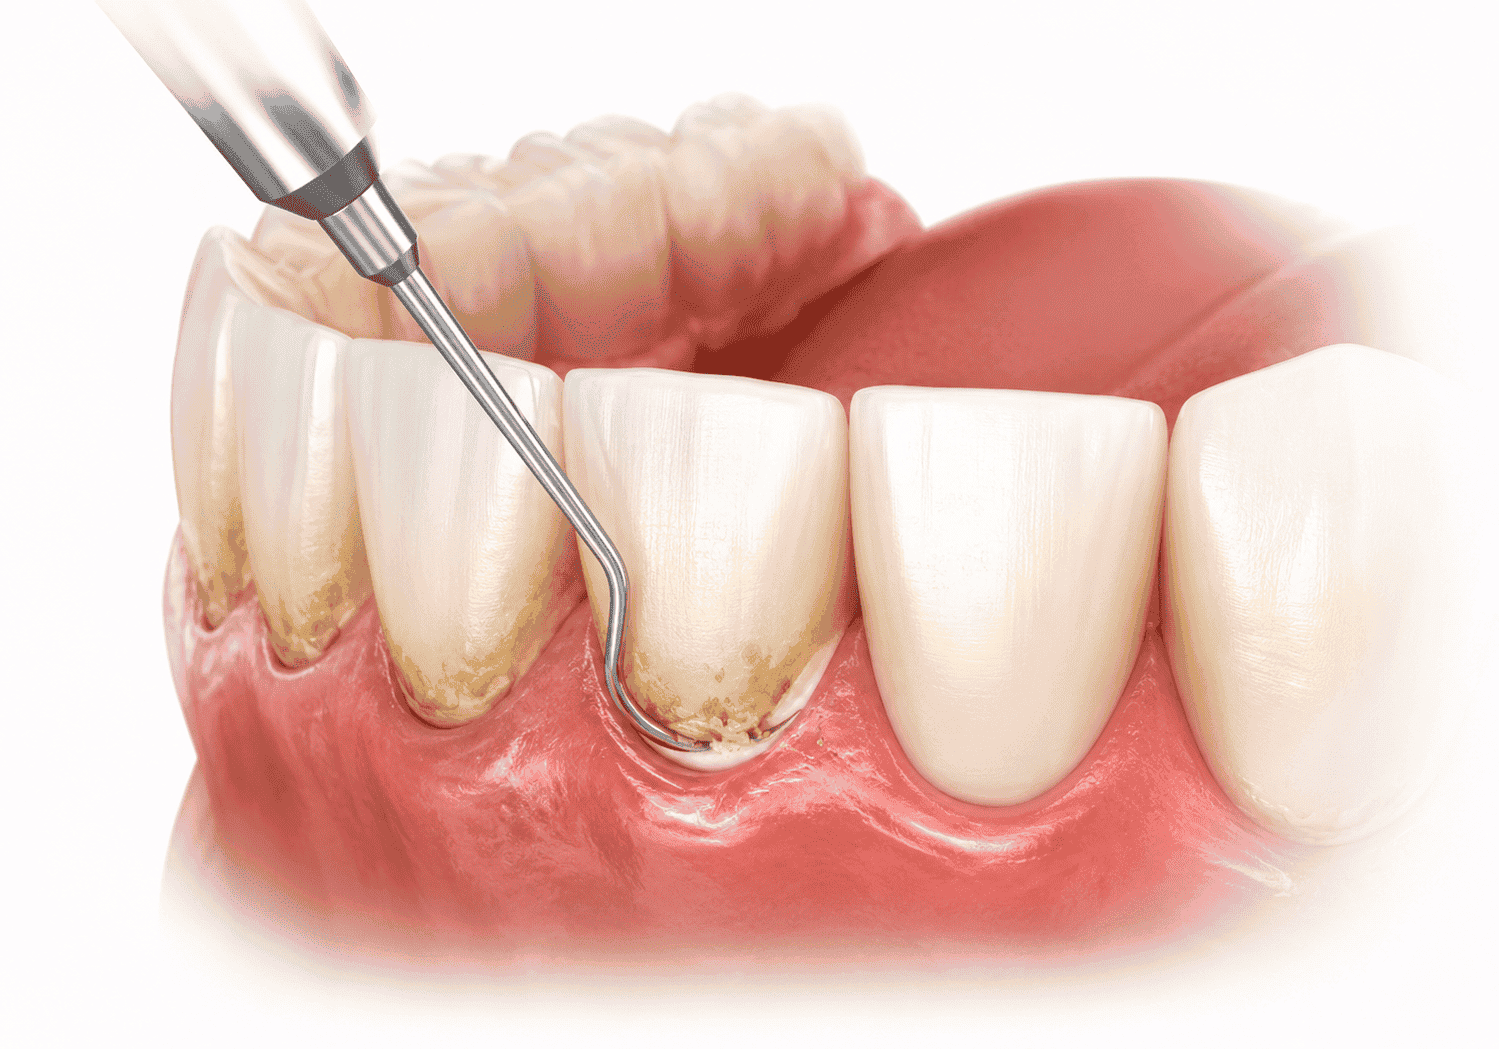

সম্পূর্ণ পেরিওডন্টাল চিকিৎসা (Total Periodontal Therapy)